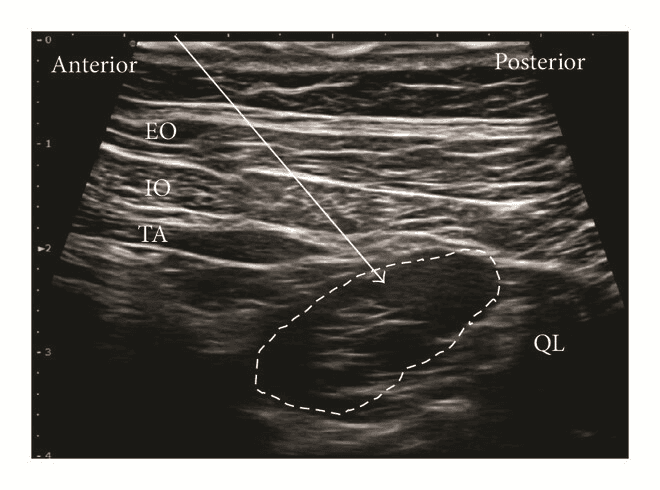

Латеральна QL-блокада (тип 1 QLВ, QLB1)

Для блокади QLB тип 1 лінійний датчик розміщують в поперечній площині по середньоаксилярній лінії, і переміщують назад доти, поки m. quadratus lumborum не стане видимим. Голку вводять in-plane з переднього або заднього краю датчика і просувають до моменту, коли вона пройде апоневроз поперечного м’яза живота, і її кінчик досягне простору між латеральною поверхнею m. quadratus lumborum та fascia transversalis. Місцевий анестетик вводять між апоневрозом і fascia transversalis біля латерального краю квадратного м'яза попереку.